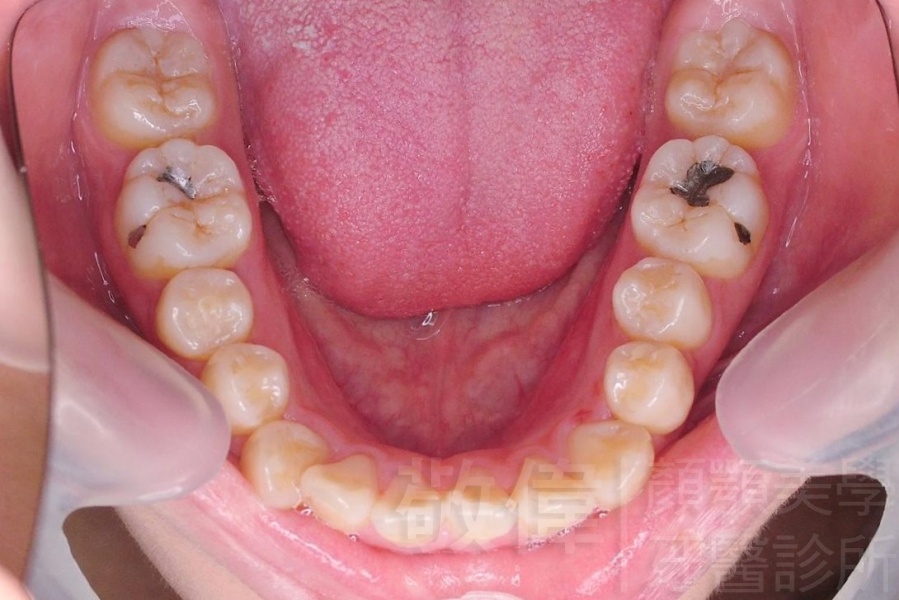

齒顏矯正/戽斗、亂牙、爛牙,變身 免植牙的健牙美女

變臉矯正,原來戽斗妹跟大歪臉變成自信正妹

經由本院3D數影X光影像儀分析、與3D齒顎顏矯正技術,再配合口腔顎面正顎專科醫師施以正顎手術治療,雙方共同合作,使患者臉部外觀有很好的改善,大歪變小歪,產生了天南地北的大改變,她的人生也整個變得不一樣。